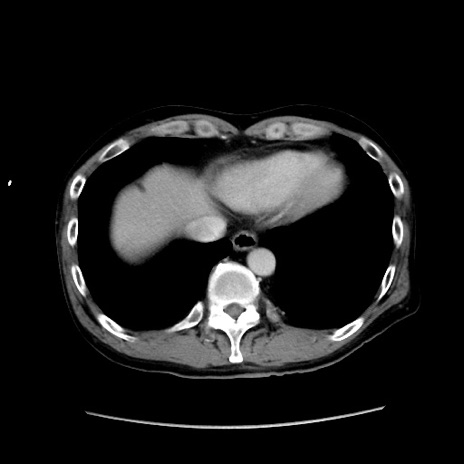

冠状断像